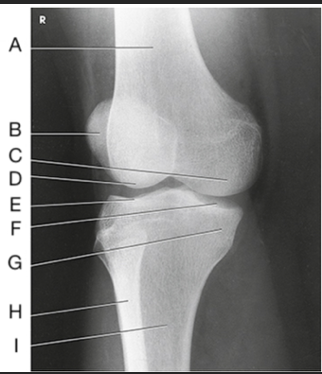

Name this projection.

AP axial IC Fossa

Name the method used.

Béclére Method

How do you know this image is a Beclere Method

Marker (line yourself up... only AP IC fossa) and is the smallest unilateral IC fossa (not elongated like Camp-Coventry and not as big as Holmblad)

Label the image: A

femur

Label the image: B

lateral condyle

Label the image: C

intercondylar fossa

Label the image: D

medial condyle

Label the image: E

intercondylar eminence

Label the image: F

tibia

Label the image: G

fibula

How does the IC fossa appear in the AP axial projection compared to the PA axial projection? (What sets the Beclere apart from the Holmblad/Camp-Coventry images?)

In Merrill's, the Beclere method makes the IC fossa look smaller. However, because we no longer have 10x12cassettes, we are forced clinically to have a larger OID in the AP axial projection, making the image look magnified compared to the PA axial projections

What are all three projections of the IC fossa looking for?

An open IC fossa (where the patellar apex is not superimposing the fossa)